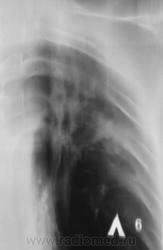

Томограмма- 1 срез.